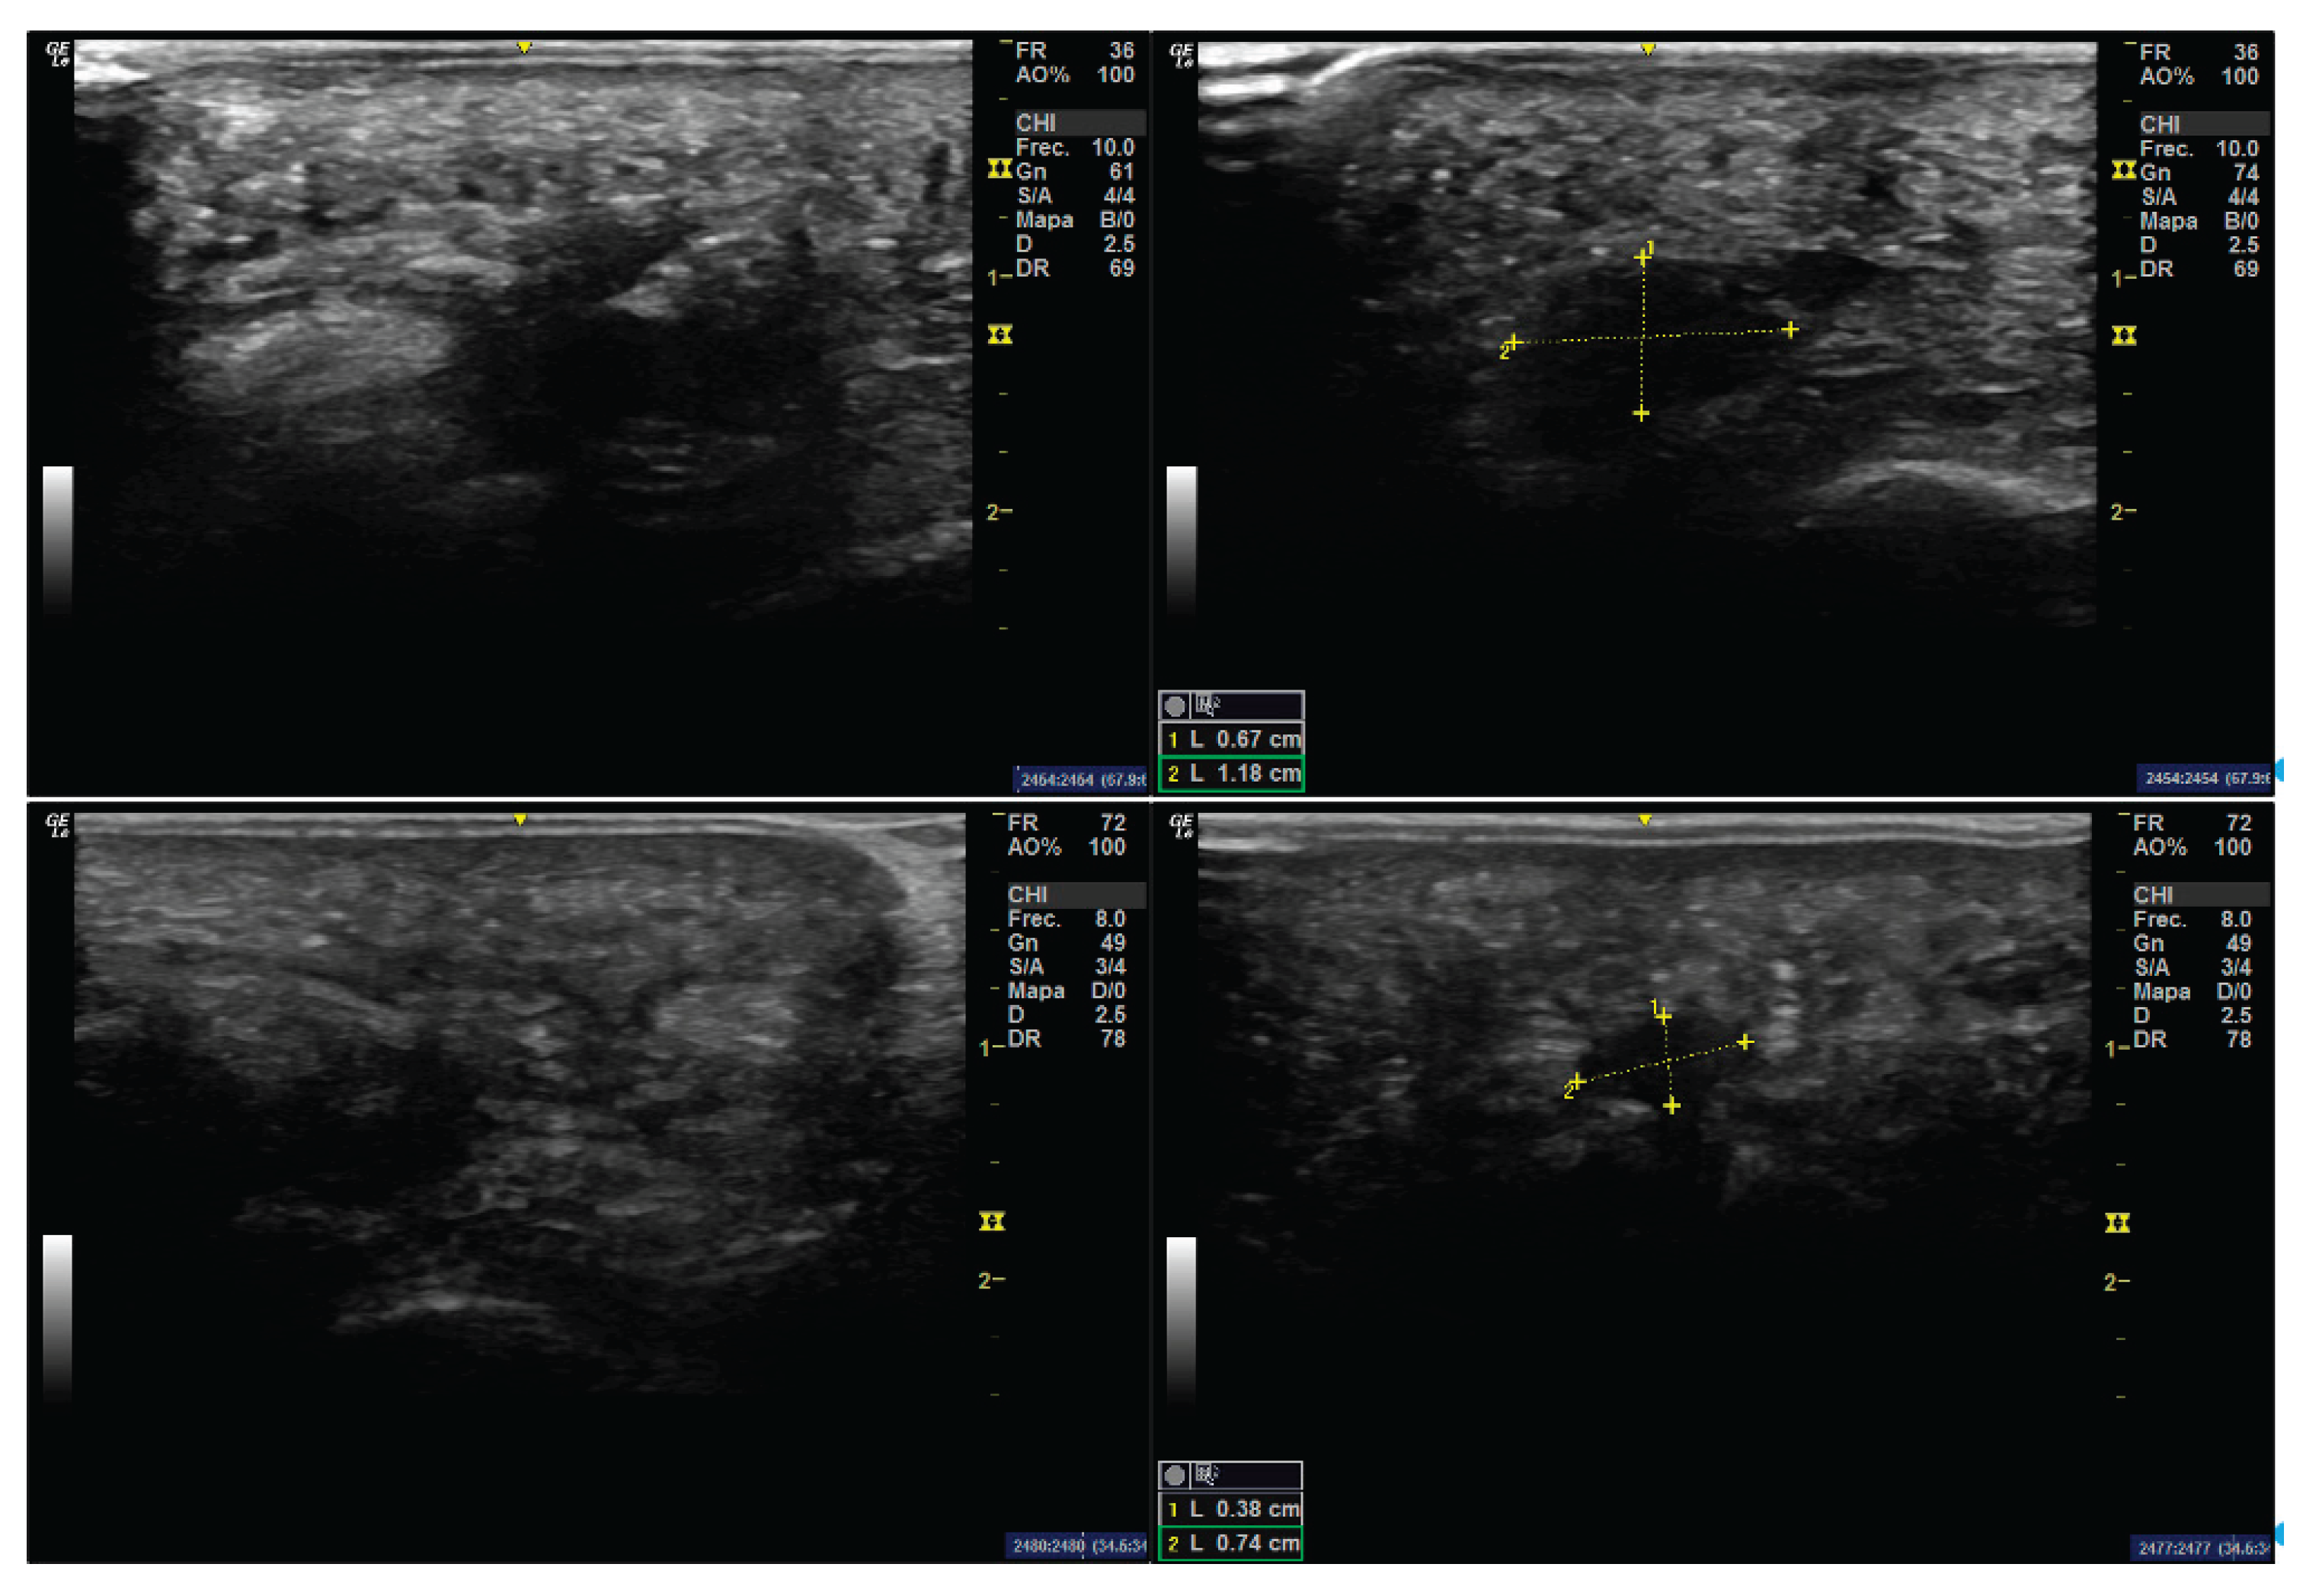

A 44-year-old female patient at the time of surgery presented with bilateral Morton’s neuroma. The neuroma in the left foot was asymptomatic, while the right foot neuroma had been associated with recurrent pain over the previous five years. No relevant medical history or known drug allergies were reported. On short-axis ultrasound imaging, the neuroma appeared as a hypoechoic mass measuring 1.18 mm in width (Figure 1), and was visualized during Mulder’s maneuver. Over the last five years, the pain had progressed from mild discomfort to a completely disabling condition during the final year, despite conservative management including orthotic interventions and corticosteroid infiltrations with betamethasone. Surgical excision of the neuroma was ultimately indicated.

A 52-year-old female patient presented with a Morton’s neuroma in the right foot, associated with a three-year history of painful symptoms. Multiple attempts at conservative treatment—including footwear modifications and custom insoles—failed to provide symptom relief. Although the patient experienced slight improvement with orthotic insoles, the outcome was ultimately unsatisfactory. In this second case, the neuroma was located in the third intermetatarsal space and measured 0.74 mm in width on short-axis ultrasonography (Figure 1). Mulder’s sign was also positive.

Figure 1. Ultrasound scans of Morton’s neuroma in the third intermetatarsal space. Top: Case 1. Longitudinal (left) and transverse (right) ultrasound views, showing a neuroma measuring 1.18 × 0.67 cm. Bottom: Case 2. Longitudinal (left) and transverse (right) ultrasound views, showing a neuroma measuring 0.74 × 0.38 cm. In both cases, a well-defined hypoechoic structure is visualized between the metatarsal heads.